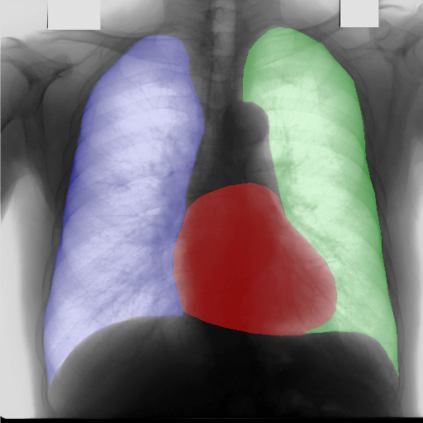

Multi-organ segmentation of X-ray images is of fundamental importance for computer aided diagnosis systems. However, the most advanced semantic segmentation methods rely on deep learning and require a huge amount of labeled images, which are rarely available due to both the high cost of human resources and the time required for labeling. In this paper, we present a novel multi-stage generation algorithm based on Generative Adversarial Networks (GANs) that can produce synthetic images along with their semantic labels and can be used for data augmentation. The main feature of the method is that, unlike other approaches, generation occurs in several stages, which simplifies the procedure and allows it to be used on very small datasets. The method has been evaluated on the segmentation of chest radiographic images, showing promising results. The multistage approach achieves state-of-the-art and, when very few images are used to train the GANs, outperforms the corresponding single-stage approach.